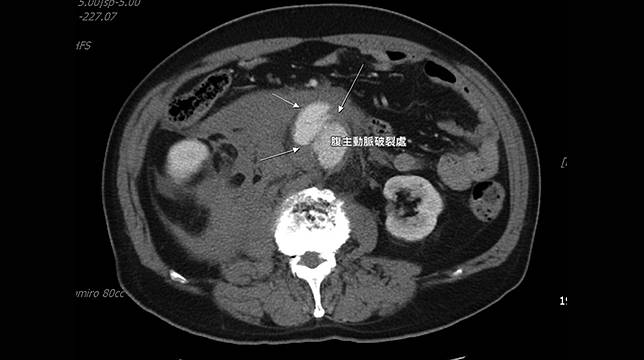

【NOW健康 傅婷/宜蘭報導】宜蘭1位67歲李先生因突發腹部劇烈疼痛至羅東博愛醫院急診就醫,經電腦斷層掃描發現腹部有顆8.2公分的腹主動脈瘤破裂,隨時有出血致死的危險,就像體內有1顆不定時炸彈爆炸,所幸在進行緊急手術治療後,搶救回寶貴性命。

▲賴韋良醫師解釋,腹主動脈瘤的產生,除非發生破裂,感到突發性的劇烈疼痛或休克、意識改變等,否則通常不容易發現。(圖/羅東博愛醫院提供)